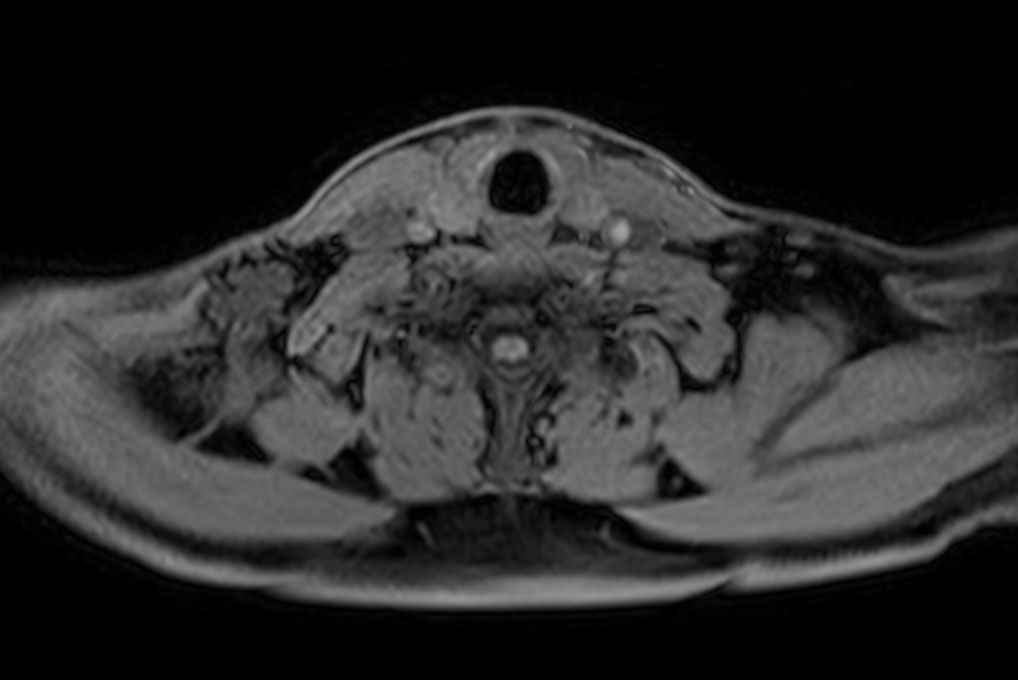

Axial T2w mDIXON XD TSE (Water only)